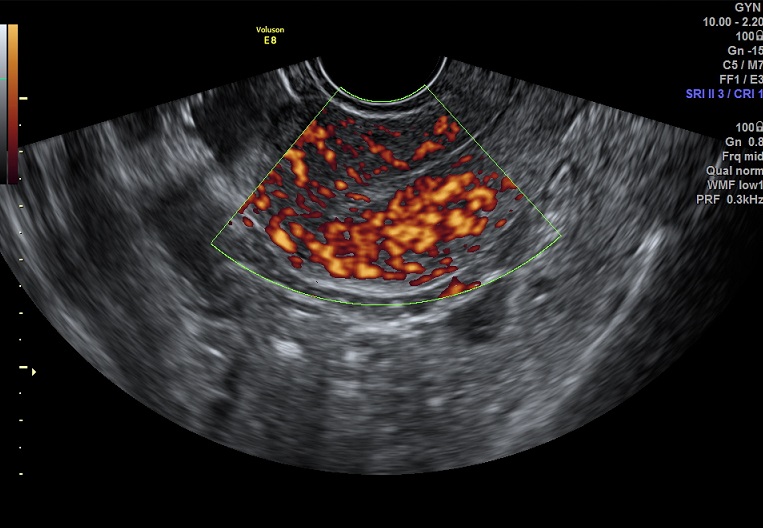

2015-2-17 月经第23天检查 黄体期 |

2015-2-17图示